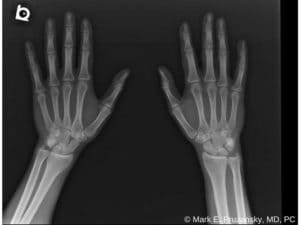

X-rays can show if a bone is broken and whether there is displacement (a gap between broken bones). Sometimes, a broken scaphoid does not show up on an x-ray right away. If this is the case, your doctor may put your wrist in a splint for a week or two. A new x-ray will be taken to see if the fracture will become visible. The splint should be worn during this waiting period, and heavy lifting should be avoided.

(Left) This x-ray shows a Scaphoid Fracture fixed in place with a screw. (Right) This x-ray was taken 4 months after surgery. The fracture of the scaphoid is healed.